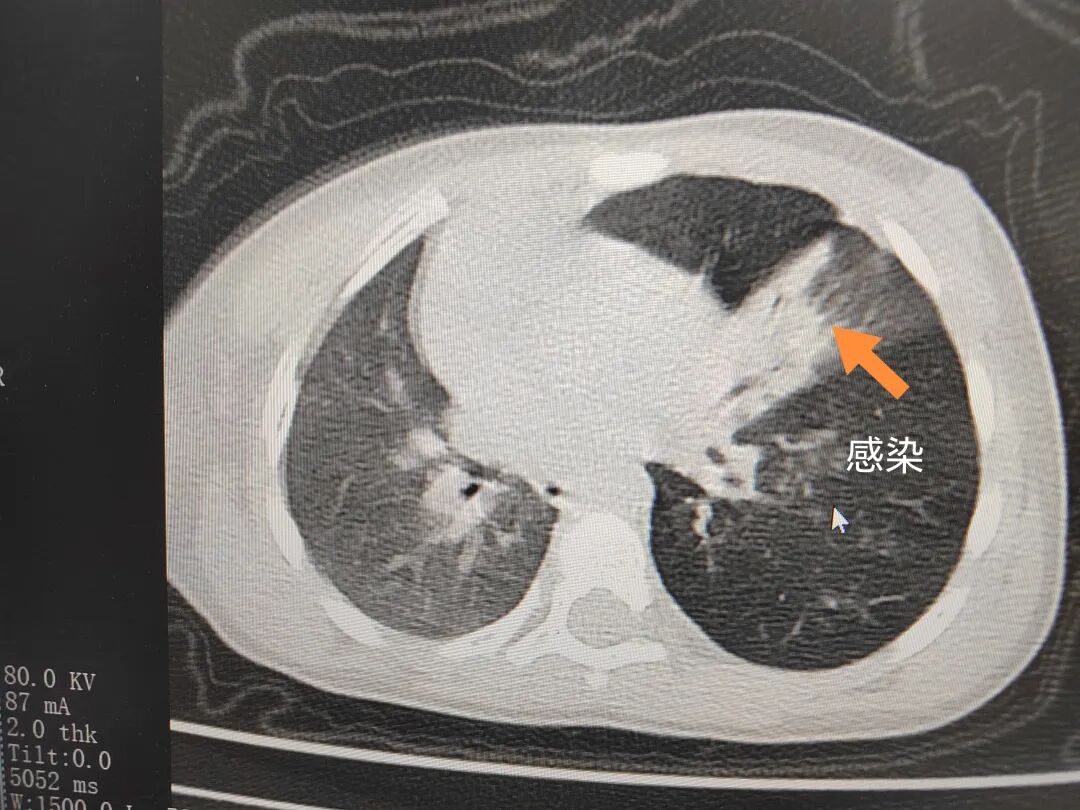

三天后(11月13日),趙寶出現(xiàn)高熱、咳喘加重,家長(zhǎng)著急了,再次帶他來到醫(yī)院。CT檢查顯示左肺過度充氣,左肺上下葉支氣管主干見不規(guī)則高密度影,左肺上葉可見大片狀密度增高影,縱隔窗實(shí)變,提示為“左側(cè)支氣管內(nèi)異物并繼發(fā)性改變,左肺上葉舌段肺膨脹不全”。

市二院小兒呼吸內(nèi)科團(tuán)隊(duì)迅速為患兒制定了周密的手術(shù)方案,并很快安排了氣管鏡探查。術(shù)中,主治醫(yī)師田慧等憑借嫻熟的氣管鏡操作技術(shù)成功將異物大塊板栗取出。由于板栗在氣管內(nèi)存留時(shí)間較長(zhǎng),質(zhì)地軟糯易碎,大大增加了手術(shù)難度。檢查還發(fā)現(xiàn),異物停留部位的氣管黏膜已出現(xiàn)充血紅腫、糜爛,導(dǎo)致患兒住院時(shí)間相應(yīng)延長(zhǎng)。此次事件給趙寶的家庭帶來了不小的驚嚇與擔(dān)憂,也再次為廣大家長(zhǎng)敲響了警鐘。

市二院小兒呼吸內(nèi)科副主任楊亞娟介紹,異物誤入氣道可能導(dǎo)致氣道阻塞,嚴(yán)重時(shí)可引發(fā)窒息,甚至危及生命。若異物進(jìn)入支氣管,造成不完全堵塞,可引起阻塞性肺氣腫;如完全堵塞支氣管,則可能導(dǎo)致肺組織萎縮,形成肺不張。此外,若異物存留時(shí)間較長(zhǎng),或?yàn)橹参镄援愇?,容易合并?xì)菌感染,產(chǎn)生膿性分泌物,進(jìn)而發(fā)展為肺炎。她強(qiáng)調(diào),盡早診斷并取出異物,是減少并發(fā)癥、降低病死率的關(guān)鍵。